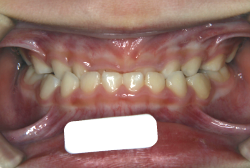

過蓋咬合

過蓋(かがい)咬合とは、奥歯を閉じた時に前歯が深く咬み込み、下の前歯がほとんど見えなくなるくらい閉じすぎになる症状です。強く咬んでいると言うことは、力が強く出て一見良さそうに聞こえますが、深く咬みすぎることは歯にも良くないですし、口腔周囲の環境としても好ましくない状態です。

「歯並びの凸凹を直したい」という主訴で来院したケースです。診断の結果、たしかに「叢生」という隙間が足りないと言うことが原因の凸凹症例でした。

しかし、それ以上に問題なのは「前歯の噛み合い方が深すぎる」という症状で、初診の歯の正面写真を見ると下の前歯が全く見えません。こういう症状を矯正学では「過蓋咬合(かがいこうごう)」と言います。過蓋咬合を放置すると、将来的に顎関節に悪影響を与えるとされており、顎関節症の原因因子の一つです。また下の前歯の先端が、上の前歯の裏側の歯茎と強く接触するため、歯周病の原因にもなります。

検査の結果、凸凹が軽症なため非抜歯で矯正すること可能と判断、マルチブラケット装置にて治療しました。治療後は歯並びが綺麗になっただけでなく、噛み合わせ的にも正しい状態が確立しています。